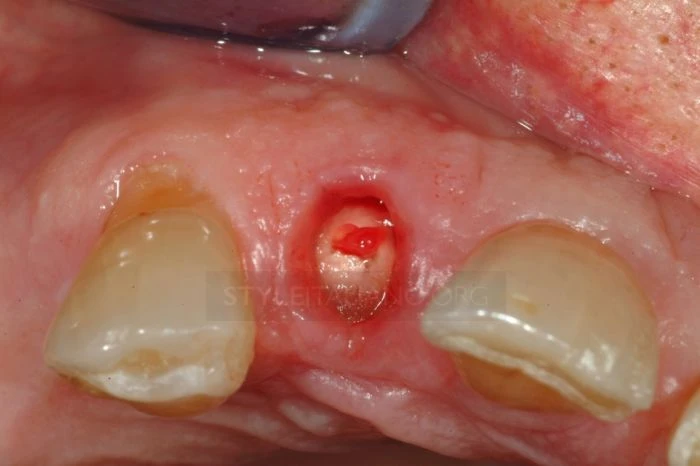

Quan xát rãnh nướu răng có hiện tượng chảy máu, xét nghiệm nhạy cảm âm tính và răng có tình trạng lung lay.

Thông qua phim X-Quang có thể thấy chân răng đã bị gãy và vị trí gãy cao hơn mào xương ổ răng, đồng thời vết gãy đã xâm nhập vào buồng bột của răng cửa bên cạnh.

Sau khi tiến hành chuẩn đoán và tiến hành gây tê tại chỗ, các bác sĩ tiến hành nhổ mảnh răng bị gãy.

Lúc này có thể thấy được đường răng bị gãy, đây là trường hợp gãy chân răng theo phân loại mới nhất.(5)

Quan sát vết gãy: có thể thấy máu chảy nhiều hơn ở phía ngoài bởi tổn thương kéo dài hơn về chóp răng khía bên ngoài.

Chú ý quan sát có thể thấy điểm hở tủy.